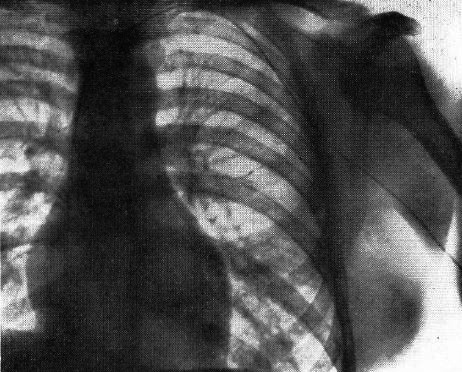

1927年に脳血管造影に成功したMonizは,さらに右心・肺動脈造影法を試みた.NaIを用いて上肢あるいは頸部表在静脈にカテーテルを挿入して造影したが,動物実験では成功したもののヒトでは造影剤が逆流して上大静脈~右心系にまで到達しなかった.丁度その折り,Forssmannの右心カテーテル法成功を知り,カテーテルを右心房まで挿入して,右心系,肺動脈の造影に成功した経緯が記されている.最後に断っているように,対象はまだ正常例のみで疾患の画像所見には言及されていない.